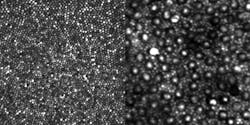

In the eye, the light-sensitive cells known as cones are concentrated at the center of the retina in the fovea centralis; they provide high visual resolution and color vision. Rods are much more numerous than cones, are more sensitive to light, and exist mainly in locations other than the fovea. The rods, which are monochrome sensors and are used in low-light vision, have previously been difficult to image clearly, even with the use of AO.

Reflectance images of a human eye were taken with a 27-year-old male emmetrope (someone with excellent vision without glasses) as the subject. The sinusoidal scan data was made linear by estimating the distortion from images of a Ronchi ruling and then resampling the data. The photoreceptor images can be displayed using a linear grayscale versus image intensity (see figure), or using a logarithmic grayscale mapping, which could be more useful for OCT.